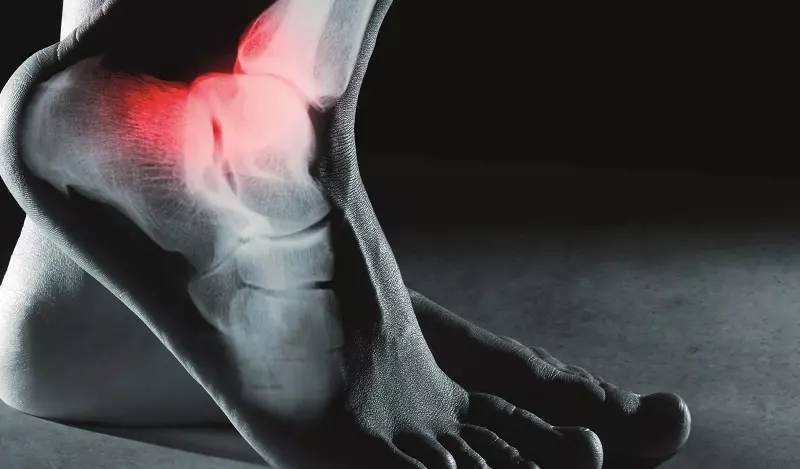

Najczęstszymi objawami złamania są: ból nasilający się przy próbie ruchu, zaburzenie funkcji, zblednięcie lub zaczerwienienie skóry, patologiczne ułożenie, deformacja, obrzęk i krwiak. Dodatkowo można zaobserwować przyspieszenie tętna, oddechu, spadek ciśnienia oraz świadomości czy wstrząs pourazowy2

Diagnostyka złamania opiera się głównie na wykonaniu oceny radiologicznej. Zazwyczaj wykonuje się zdjęcie rentgenograficzne (RTG) w dwóch projekcjach – przednio-tylnej lub tylno-przedniej, bocznej lub osiowej. Dodatkowo w przypadku uszkodzenia tkanek miękkich przeprowadza się badanie ultrasonograficzne (USG), tomografię komputerową (TK) czy też rezonans magnetyczny (RM) lub badanie artroskopowe3 4.